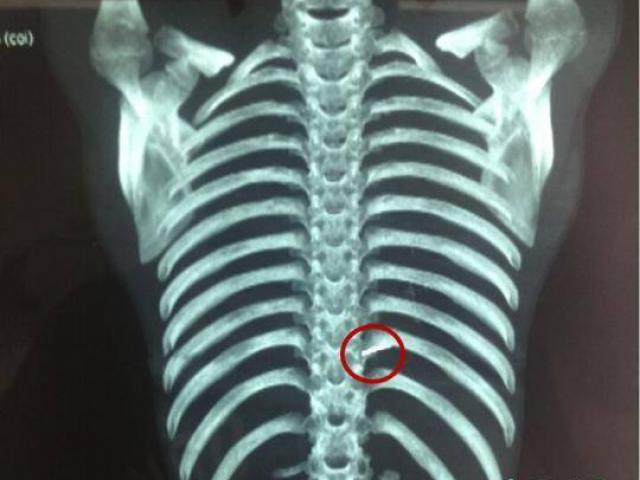

BS Bùi Trung Dũng, Phó khoa Răng Hàm Mặt - Mắt, cho biết bệnh nhân nhập viện trong tình trạng vết thương kéo dài từ dưới mắt trái qua mắt phải, vỡ nhãn cầu trái, tổn thương mắt phải, gãy xương mũi, rách niêm mạc mũi, gãy xương hàm hai gò má chia mặt ra làm đôi, chảy máu nhiều..

Theo BS Dũng, với cơ chế gây chấn thương có thể đoán sau khi bơm quá căng, bánh xe phát nổ và mâm bánh xe văng vào mặt bệnh nhân với áp lực rất lớn. Đây là lần đầu tiên BV tiếp nhận bệnh nhân bị tổn thương nặng như vậy do "xe rùa" gây ra.